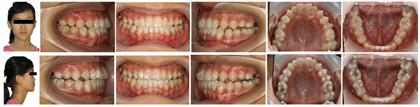

正面观面部不对称,侧面观为凹面型,下颌前突,替牙列,双侧尖磨牙呈近中关系,反覆盖反覆合,Spee曲线深,下颌不能后退至切对切。

正面观:面部不对称,左侧面颊部较宽,颏点偏左。侧面观:凹面型,面中份略凹陷,下颌前突,颏唇沟浅。

口腔卫生一般,牙龈轻度肿胀,替牙列期,牙列式:

,其中

反覆合反覆盖。双侧尖磨牙近中关系,反覆盖3.7 mm,反覆合3.6 mm。上中线基本对齐,下中线左偏2 mm。上颌牙弓宽度略不足,下前牙舌倾,根形明显,薄龈型。12,22过小牙。舌体,扁桃体,唇舌系带未见明显异常。

总治疗周期30个月,其中TIPA矫治18个月,隐形矫治12个月。矫治后患者侧貌由凹变直;上下牙排列整齐,牙列无间隙,双侧尖磨牙中性关系,前牙覆合覆盖正常,上下牙弓形态位置关系协调,咬合稳定无干扰(图6)。

侧貌由凹变直;上下牙排列整齐,牙列无间隙,双侧尖磨牙中性关系,前牙覆合覆盖正常,上下牙弓形态位置关系协调,咬合稳定无干扰。髁突表面发生功能性改建,髁突位置稳定,关节间隙正常。